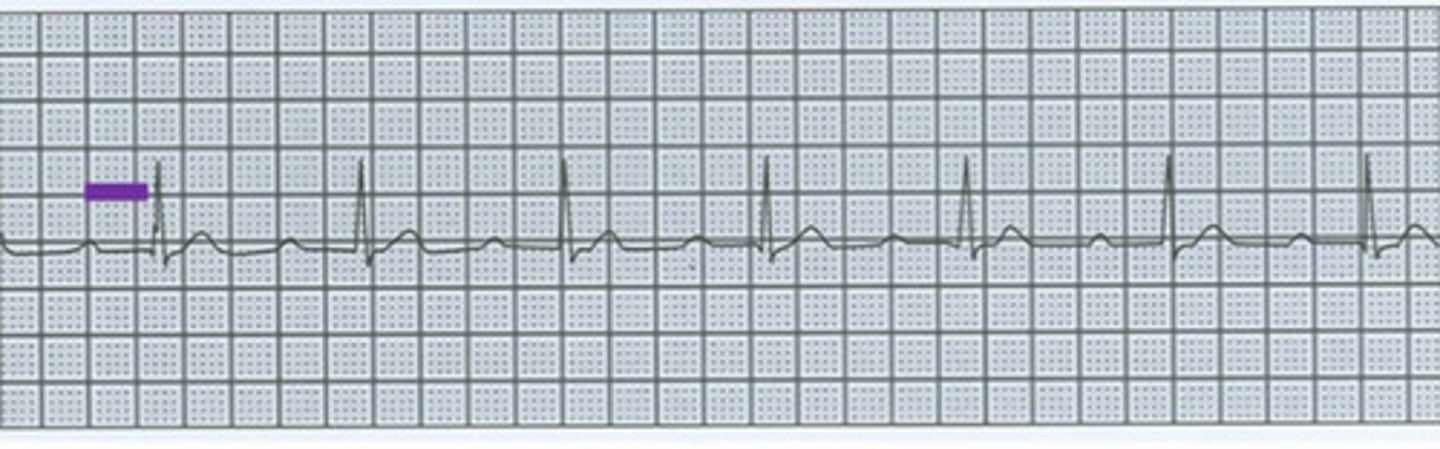

What is causing this ECG?

Hyperkalemia

What is abnormal about these waves?

1. Absent P wave

2. Tall peaked T wave

3. Wide normal QRS